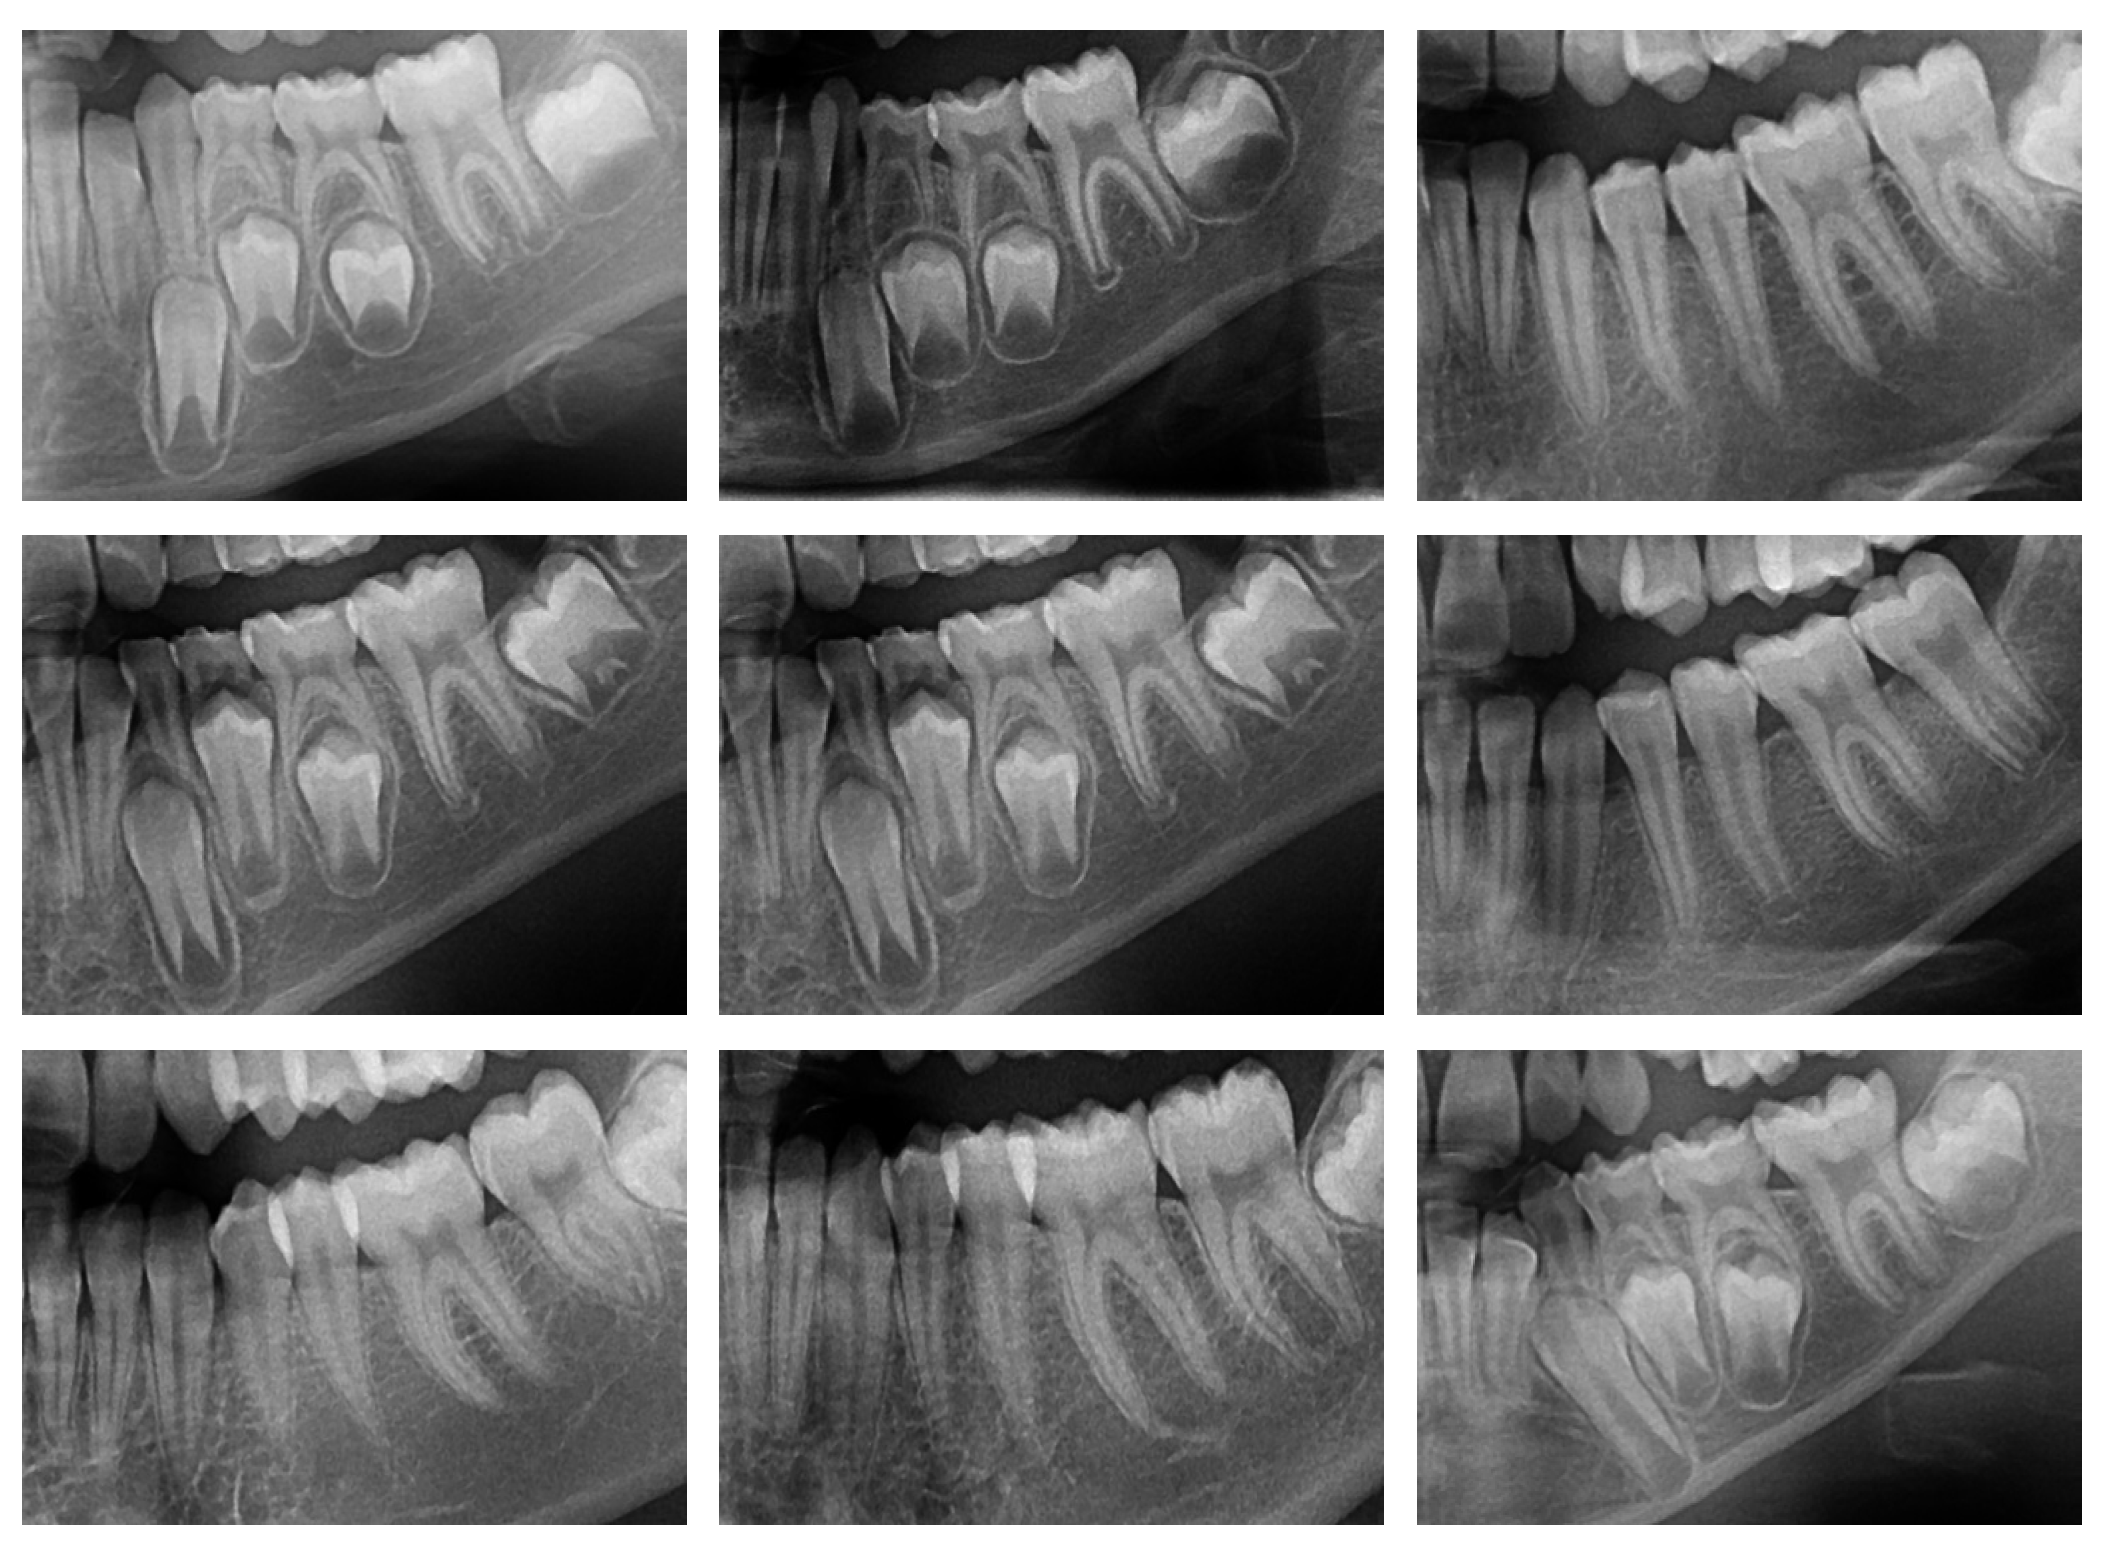

This study comprises of OPG images and patient records within the dataset. Real-time dataset is considered for this research work. Some sample OPG images from the dataset is shown in Figure 4. Out of 275 male, average age has been 10.94, while, out of 346 female, average age has been 11.1.

Figure 4. Sample OPGs from the dataset.